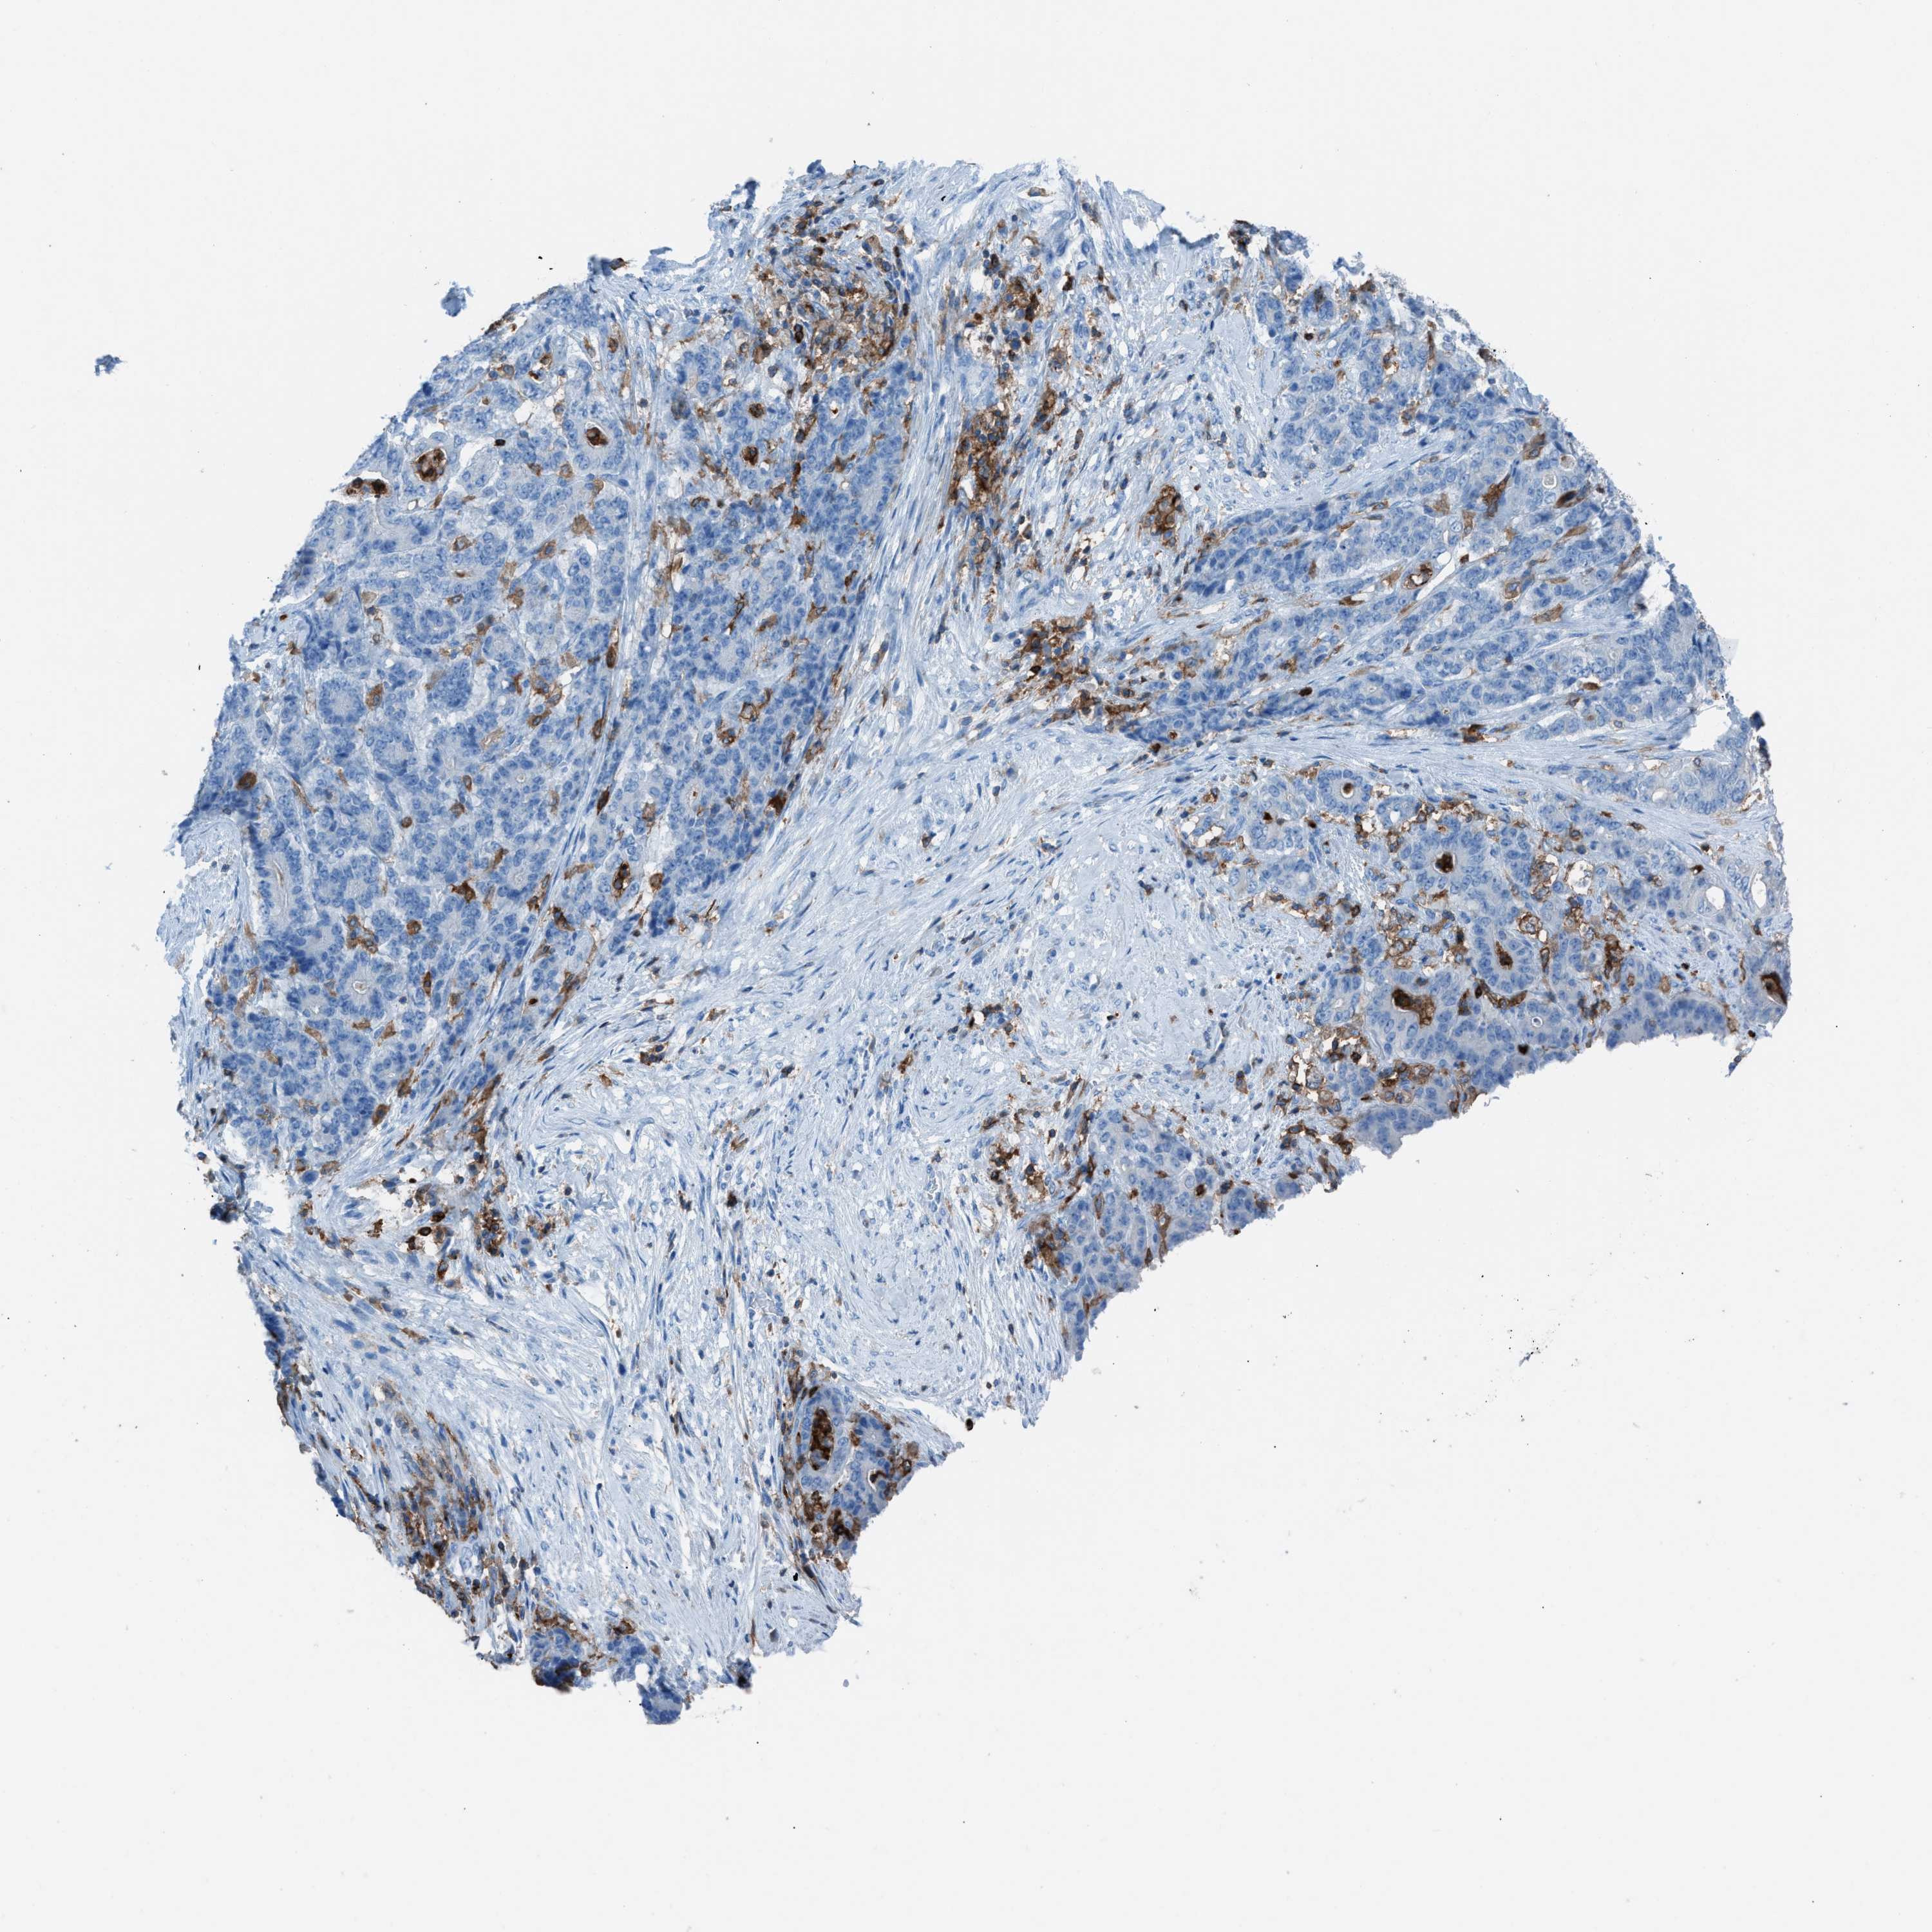

STOMACH CANCER - Protein expressioni

A mouse-over function shows sample information and annotation data. Click on an image to view it in a full screen mode. Samples can be filtered based on level of antibody staining by selecting one or several of the following categories: high, medium, low and not detected. The assay and annotation is described here.

Note that samples used for immunohistochemistry by the Human Protein Atlas do not correspond to samples in the TCGA dataset.

Antibody stainingi

Antibody staining in the annotated cell types in the current human tissue is reported as not detected, low, medium, or high, based on conventional immunohistochemistry profiling in selected tissues. This score is based on the combination of the staining intensity and fraction of stained cells.

Each image is clickable and will lead to virtual microscopy that enables deeper exploration of all samples and also displays staining intensity scores, fraction scores and subcellular localization as well as patient and tissue information for each sample.

Antibody HPA008877

Antibody HPA016894

Staining

High

Medium

Low

Not detected

Intensity

Strong

Moderate

Weak

Negative

Quantity

>75%

75%-25%

<25%

None

Location

Nuclear

Cytoplasmic/membranous

Cytoplasmic/membranous,nuclear

Adenocarcinoma, NOS